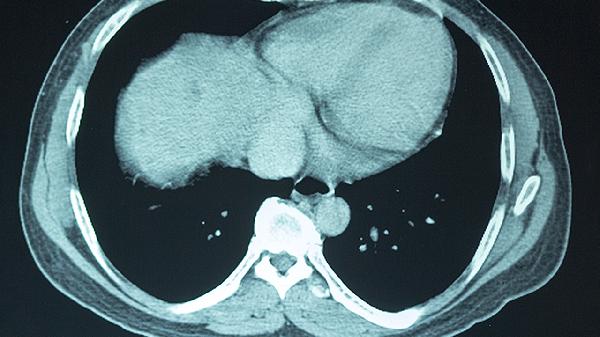

伤后1周、1个月需神经外科随访,必要时进行CT或MRI检查评估恢复情况。学生及运动员恢复学习训练前需经专业评估。遗留注意力不集中等症状时,应接受认知功能康复训练。